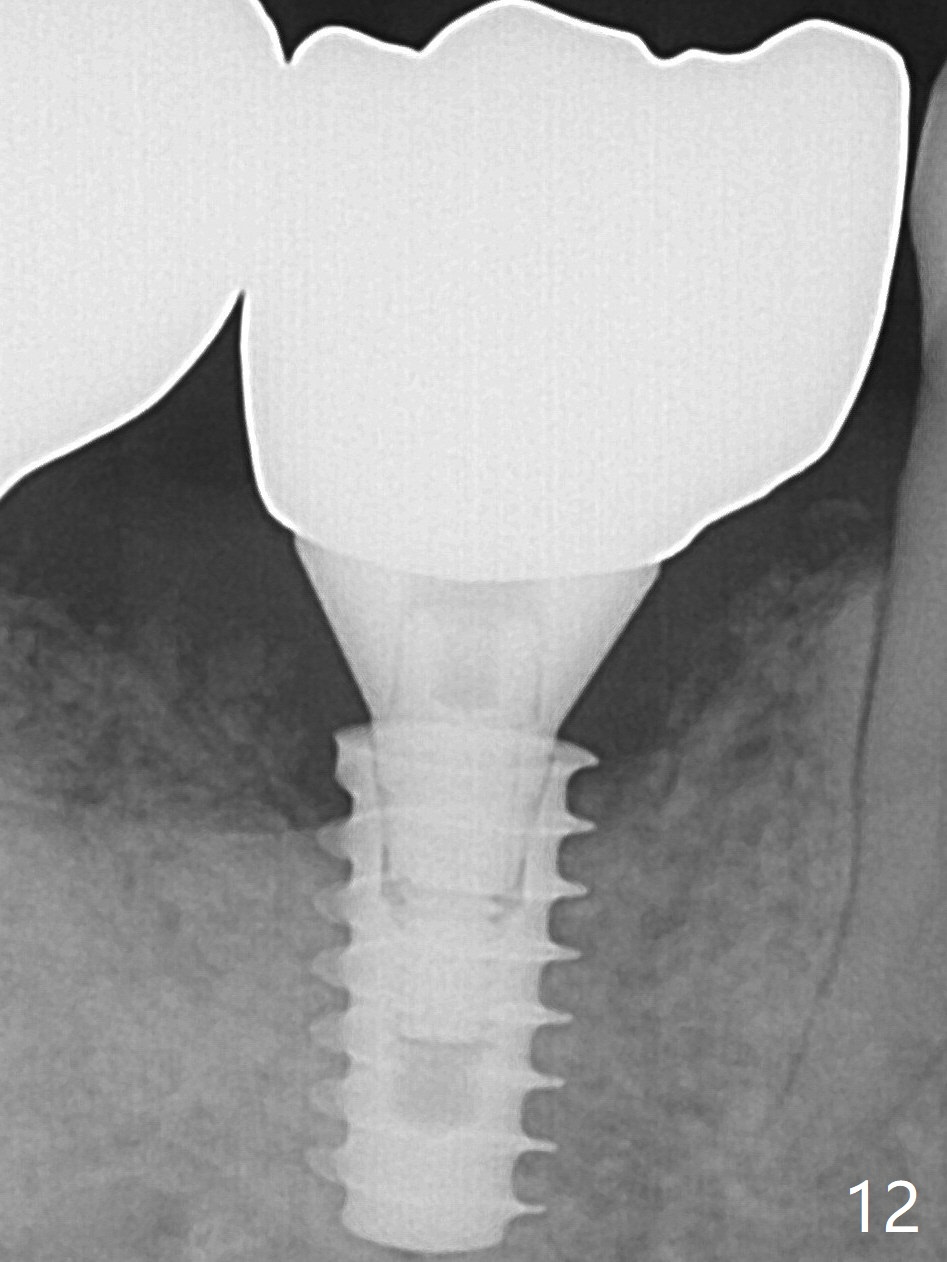

A 5x9 mm implant is placed with packing abundant allograft (.5-1.5 mm) and Osteogen; it appears that 3 to 4 threads (fins) of the implant are engaged to the native bone for primary stability (>40 Ncm). Later more bone graft is placed distally (Fig.5 arrow). Abutment: 6.5x5.5(4) mm. The patient in fact masticates on the right side postop. By the time he returns for provisional revision 1 months 10 days postop, he has mild pain. There is food entrapment. The provisional and the abutment are slightly loose, whereas the implant is stable with healing socket. A healing abutment (6x4 mm) is placed. The implant appears unstable nearly 5.5 months postop. The gap between the bone and implant seems to be large (Fig.9). The implant should have been larger and longer for fast healing. A healing screw is used instead. The site heals 10 months postop with an increase in bone density around the implant (Fig.10). In fact the abutment screw becomes loose 2 months post cementation (1 year postop); it appears that crown/implant ratio is unfavorable (Fig.12). The implant is slightly placed distally (cantilever). The tooth #18 is missing (unilateral mastication). The abutment screw is re-loosening 1.5 years post cementation (4 months post #19 socket preservation, Fig.13).